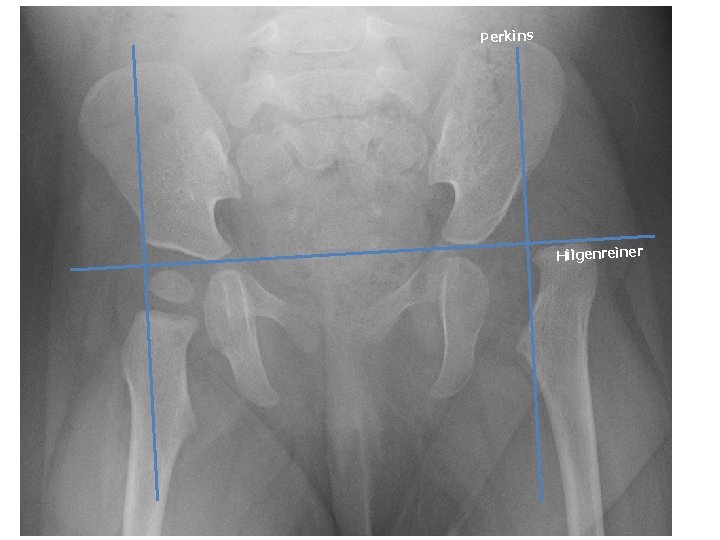

Perkins Hilgenreiner